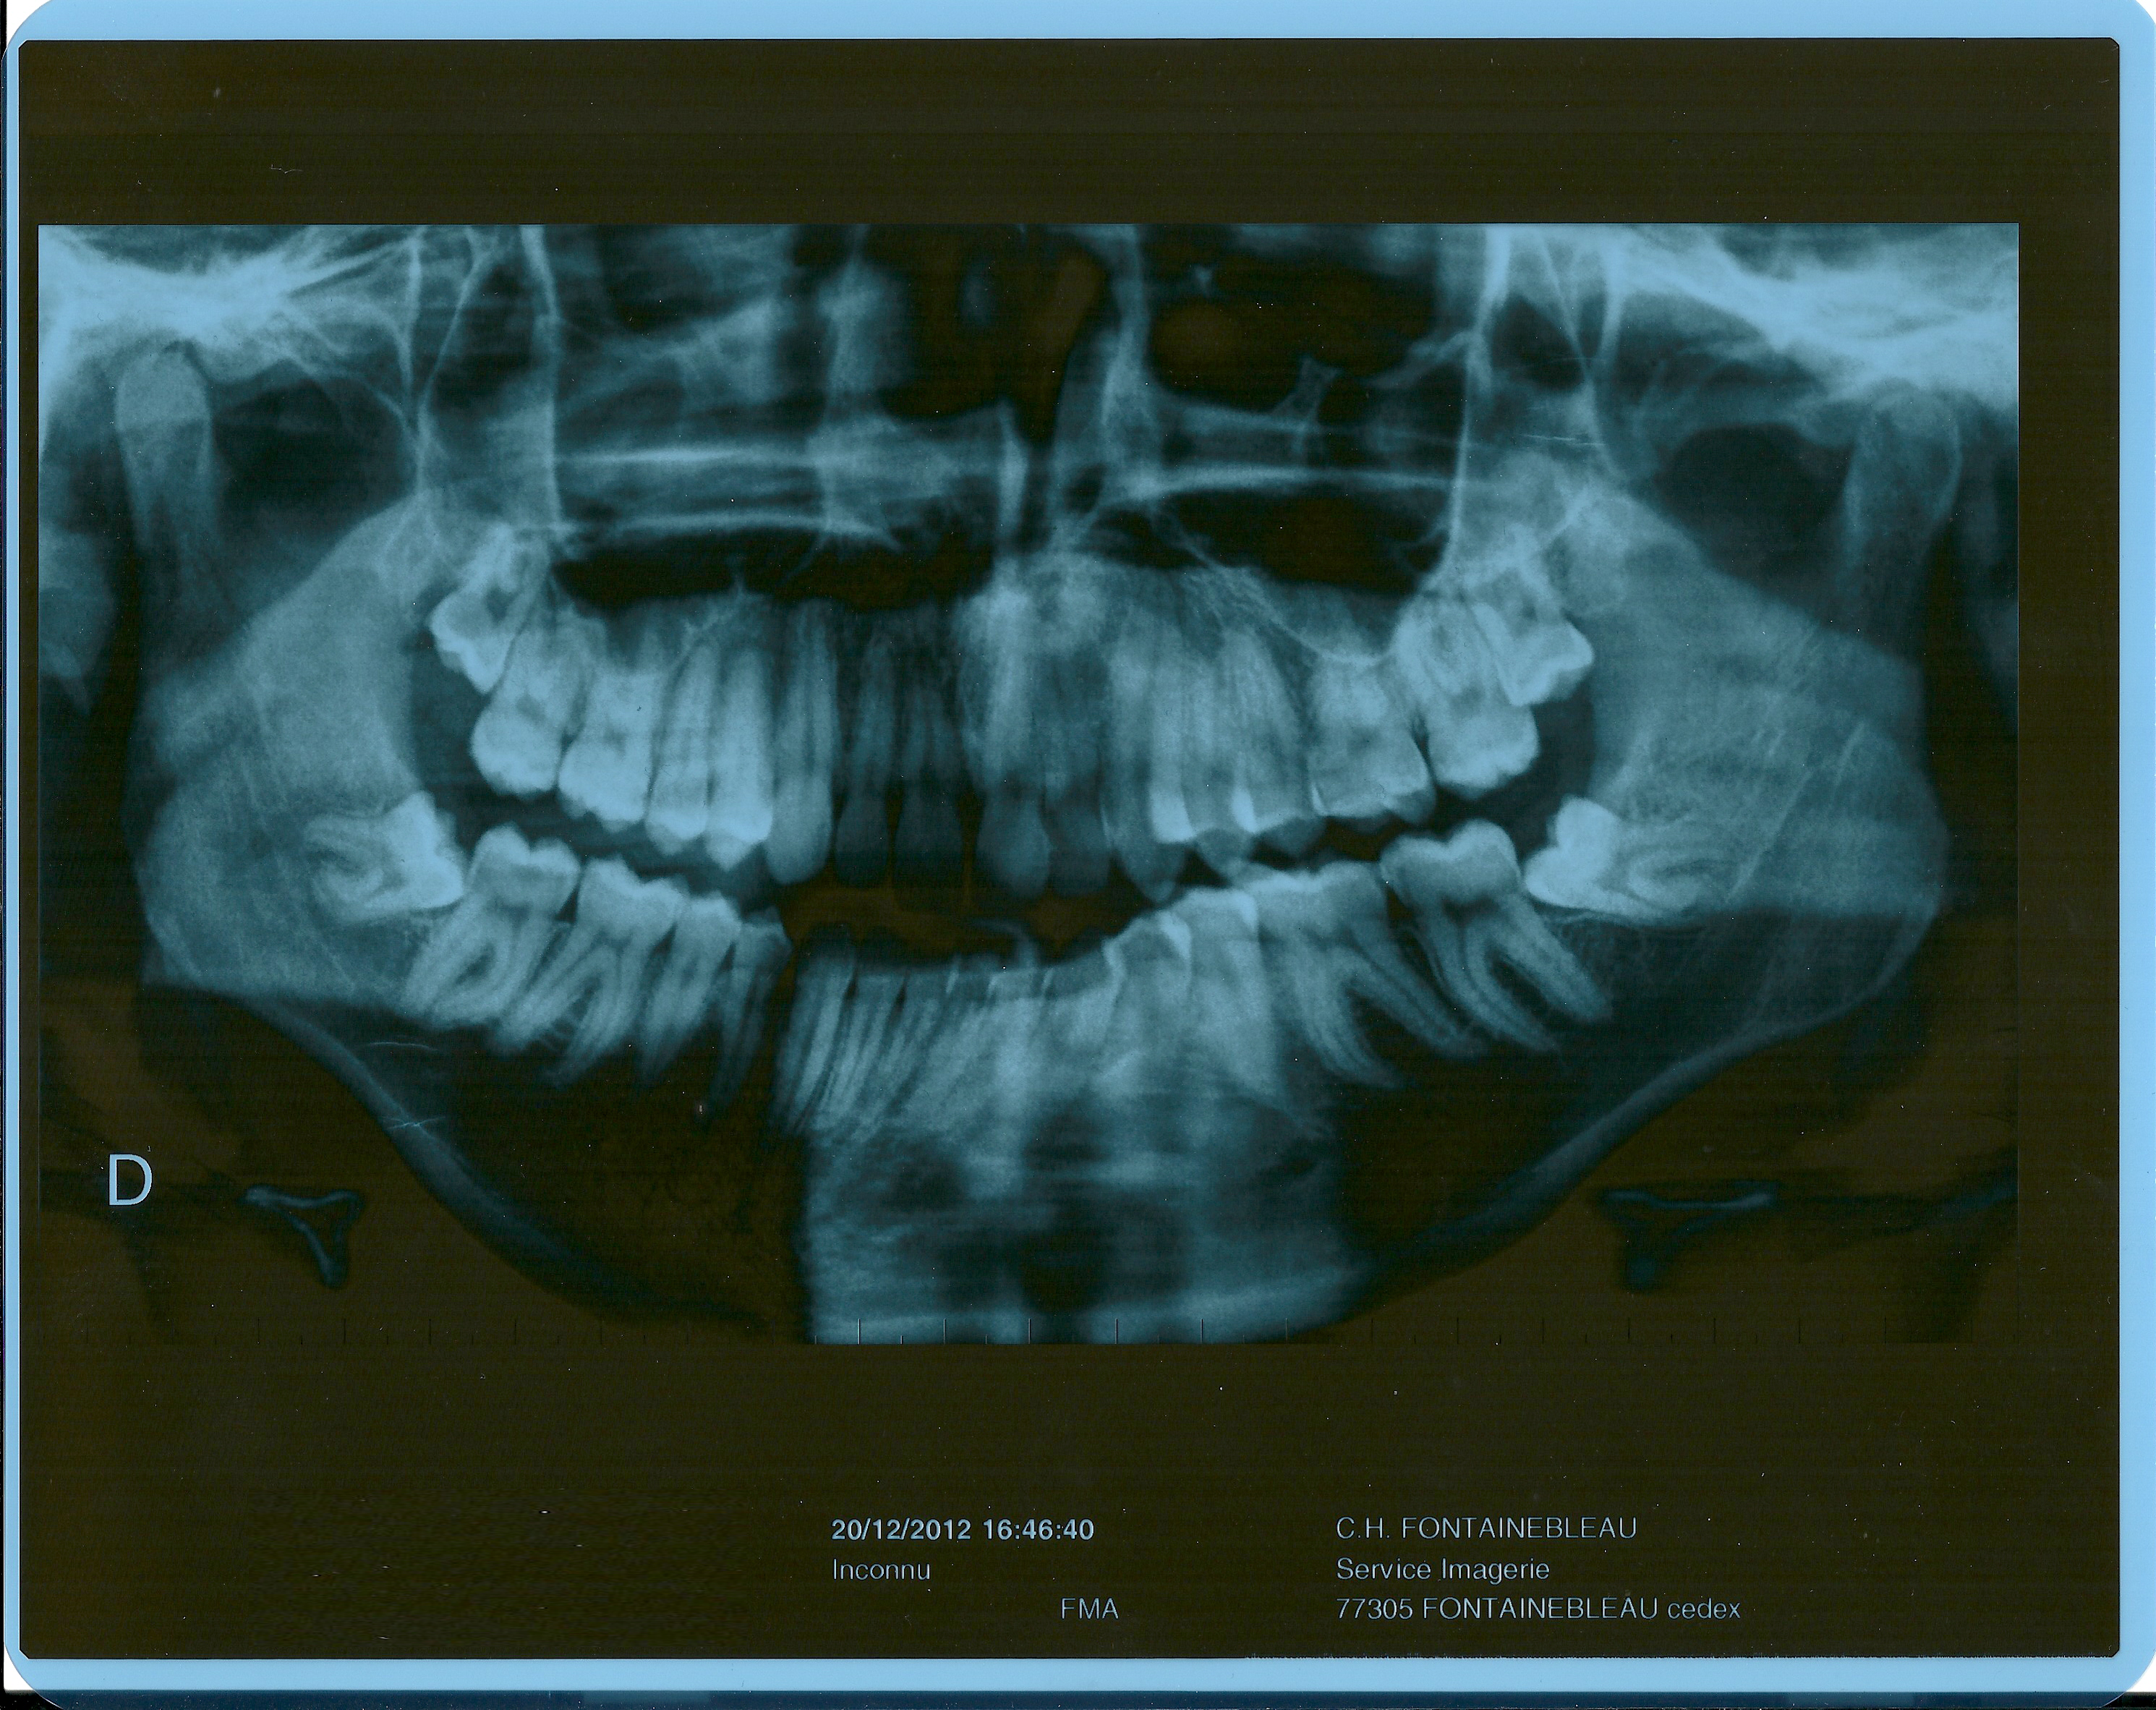

La question est Y a t'il des traitements par la suite, appareil ou juste laisser comme ça et attendre que les 2 dents définitives poussent je suis dégoutés et je suis perdu car au urgence il sont même pas fait de radio et je me suis fait dégager par mon dentiste en disant qu il ne traitait pas ce genre de chose et ma donné. Dent semiincluse il s’agit d’une dent de sagesse qui pousse et dont une partie est visible en bouche et dont l’autre partie est sous la gencive Dent éruptée dans ce cas, il s’agit d’une dent de sagesse qui pousse naturellement et qui est sortie Elle ne pose pas plus de problèmes que le reste de nos dents. Lorsqu’elles grandissent, les dents adoptent une position qui reflète les pressions qu’elles subissent dans les trois directions de l’espace dans lesquelles elles sont contenues.

Accueil Forum La communauté. Je viens d'aller chez le dentiste avec ma fille et elle m'a dit qu'elle a une mâchoire qui est trèstrop petite du coup ses 2 nouvelles dent d en bas, il y en a une qui pousse complètement de travers Elle m'a dit qu il faudra certainement lui mettre un appareil dentaire. Les dents, clés du développement, Dent qui pousse dent qui parle, Estelle Vereeck, Quintessence Holoconcept Des milliers de livres avec la livraison chez vous en 1 jour ou en magasin avec 5% de.